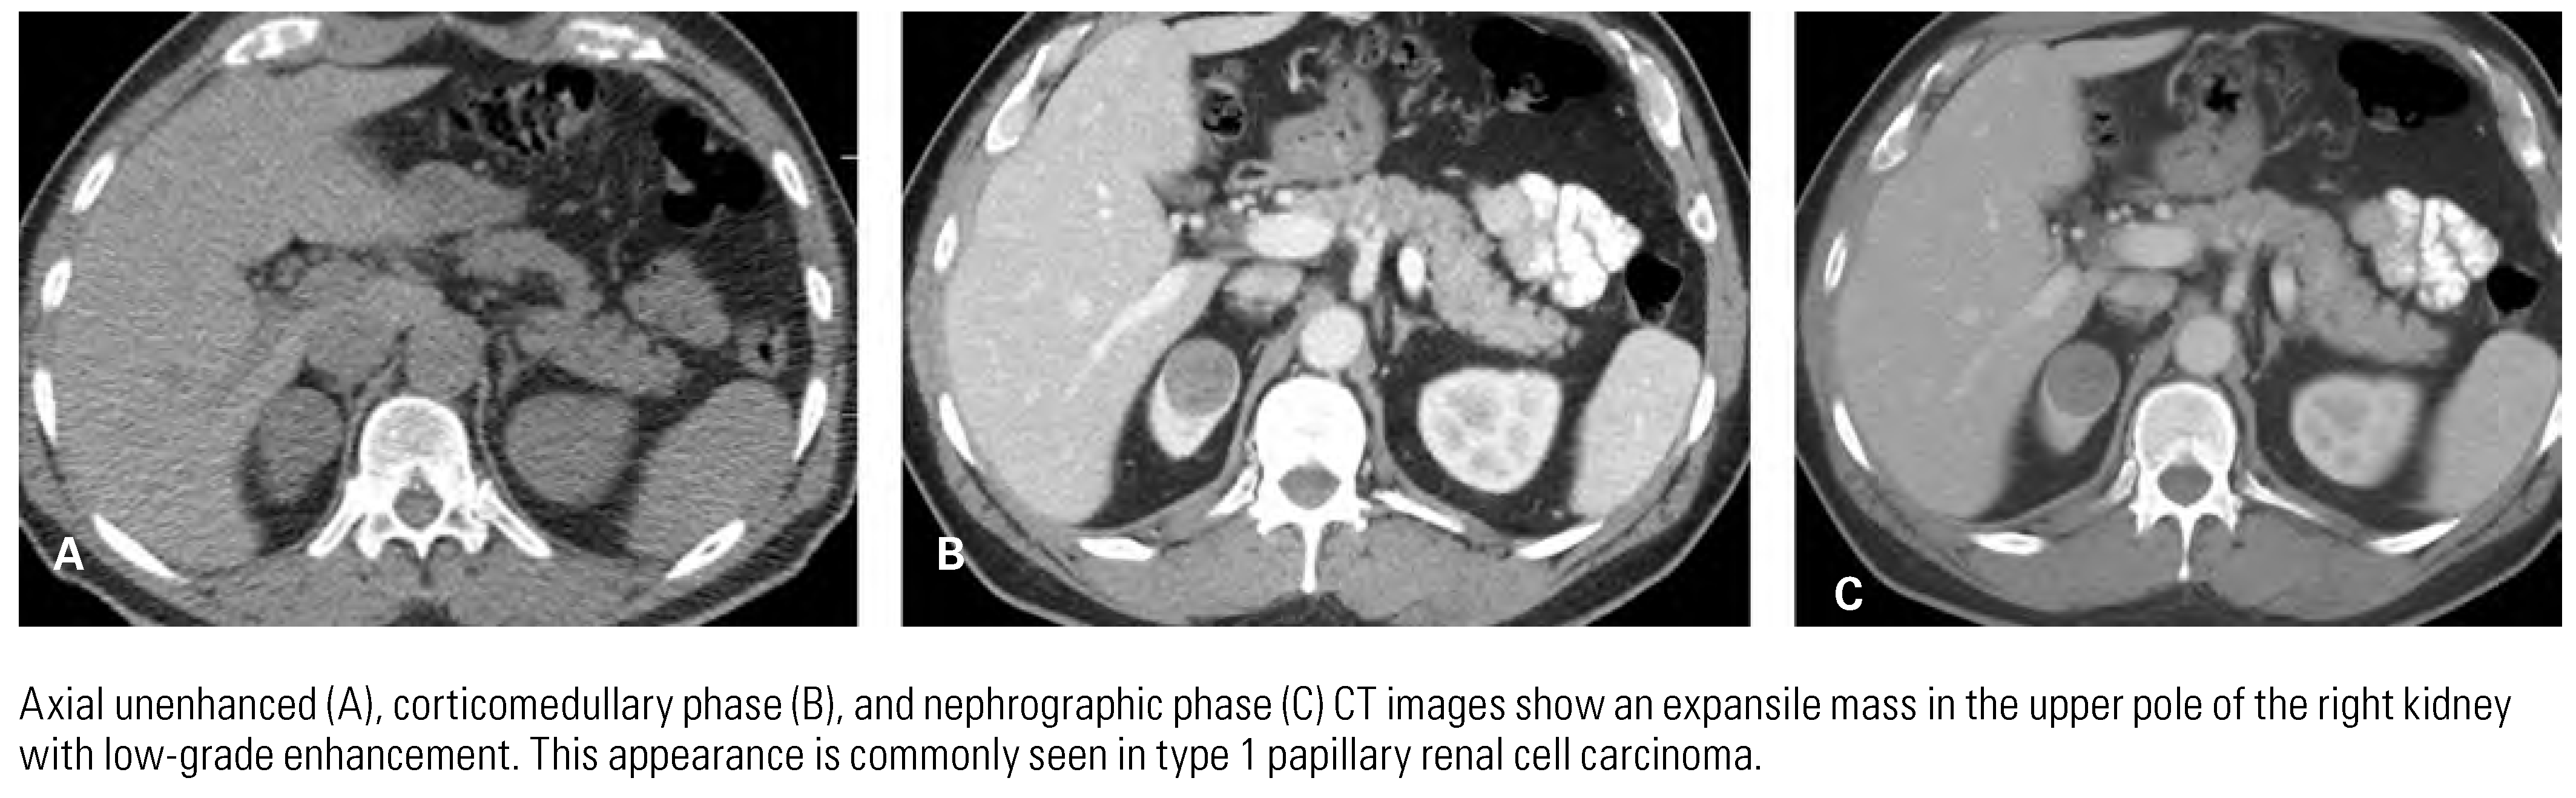

Papillary Renal Cell Carcinoma